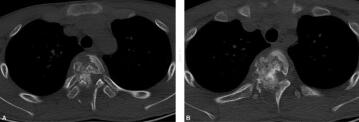

图1 CT:胸2椎体及附件骨质破坏,呈菜花状改变,胸2椎体受累,部分碎骨块突入相应椎管内,椎管狭窄